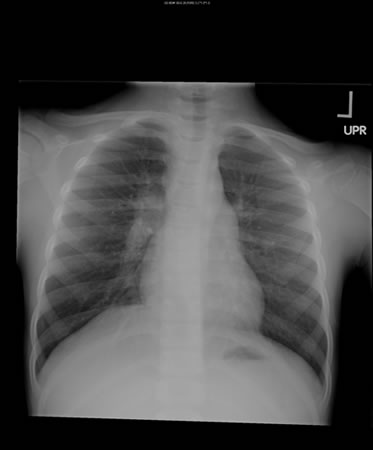

Pulmonary tuberculosis

Right hilar adenopathy in a child

From the personal collection of David Horne and Masahiro Narita; used with permission